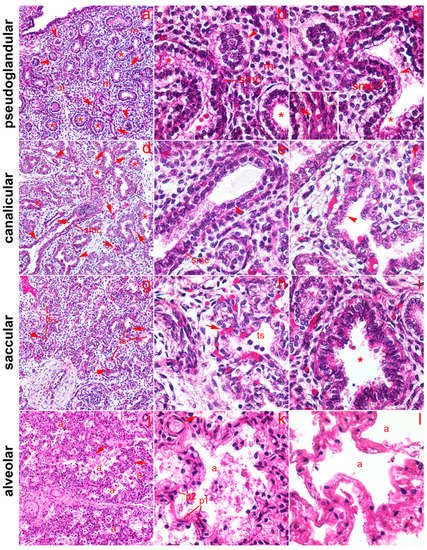

2.1. General Remarks

2.2. 5-HT1A Expression

2.3. 5-HT2A Expression

2.4. 5-HT3A Expression

2.5. Expression of Serotonin Receptors in Pneumocytes